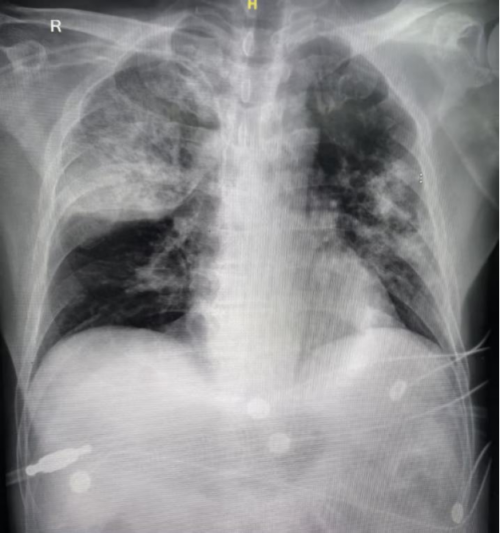

胸部CT:双肺炎症。

11月10日: